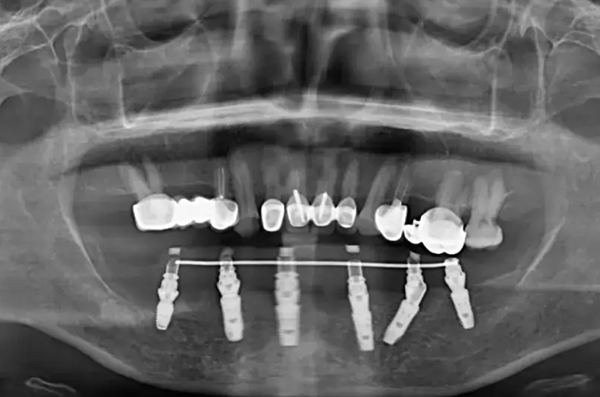

種植牙,俗稱種牙,是一種較新的成熟的口腔修復治療方法,其方法是在缺失牙的頜骨內(nèi)通過小手術植入鈦金屬的人工牙根(即種植體),使其與頜骨愈合為一體,然后在人工的牙根上鑲裝假牙(即義齒),以恢復牙列的完整性和缺失牙的功能,還你明眸皓齒。